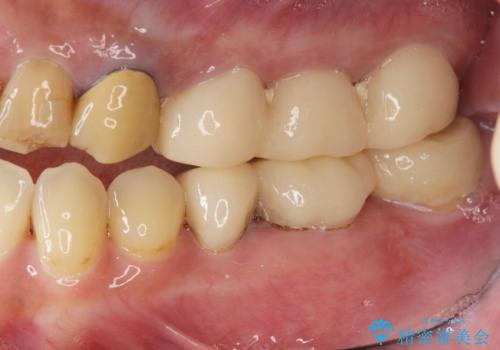

安定する噛み合わせの位置を探りながらの治療となりました。

最終的に非常に安定した咬合関係を構築できたので、しっかりとどんな食事でも楽しめると同時に、清掃性も高く清潔な口腔内環境を確立できました。